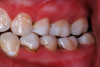

(1.) Hypocalcified/carious first molar, 12 months after SDF application.

Figure 1

SDF was developed in Osaka, Japan, in 1969.24,25 During the next 5 decades, its use and related research spread around the world.26-32 Various formulations of SDF (Bioride®, Densply Industria e Comericio Ltda; e-SDF, Kids-e-Dental Llp; Riva Star, SDI; Saforide®, Toyo Seiyaku Kasei Ltd) have been developed in different countries to attenuate dental caries infections. In 2014, an SDF solution made up of 62% water, 25% silver, 8% ammonia, and 5% fluoride (Advantage Arrest® Silver Diamine Fluoride 38%, Elevate Oral Care, LLC) was the first to gain approval by the US Food and Drug Administration to be used in the United States as a tooth desensitizing agent33; however, others have since been cleared as well. Its ability to affect dental caries pathodynamics has developed into an exceedingly popular off-label use by dentist clinicians. Figure 1 depicts an example of a malformed and carious permanent first molar that had been treated with SDF followed by 2.5% sodium fluoride varnish 6 months and 12 months prior when it was only partially erupted. This strategy attenuated the caries infection for over a year, until the patient, an extremely anxious 7-year-old boy, was able to tolerate routine restorative treatment.